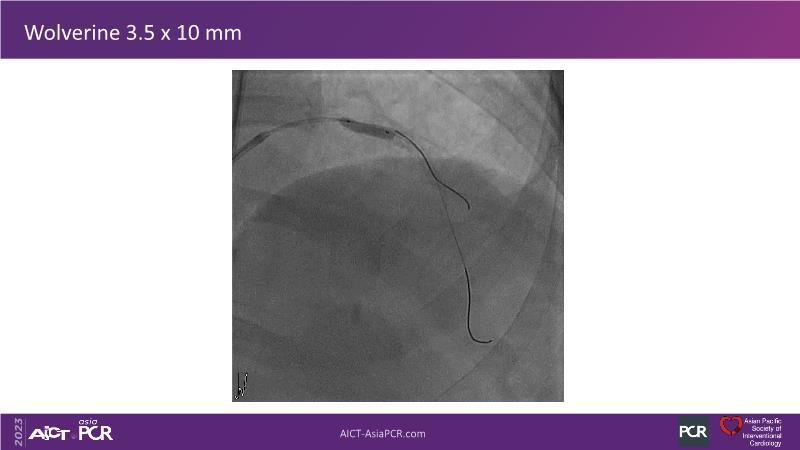

This session is recommended for you if you are seeking insights into the advantages of using IVUS imaging over visual assessment for better outcomes in left main bifurcation procedures. Discuss with experts the benefits of using RotaCUT in lesion preparation for left main bifurcation and explore the impact of high radial strength stents on the procedure's success.

• To know how a high radial strength stent can make a difference in left main bifurcation